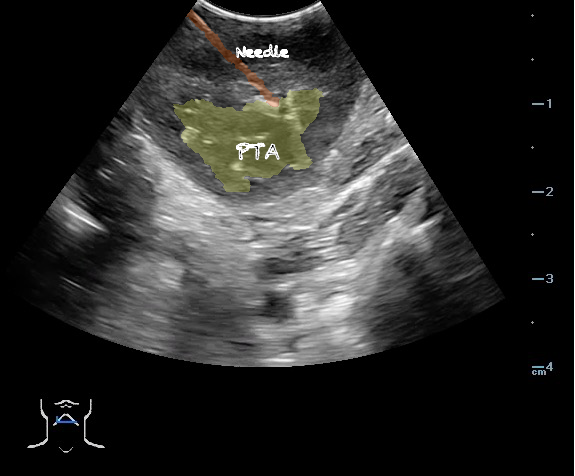

- Peritonsillar abscess is visualized as a hypoechoic or complex cystic structure

- Ultrasound-guided needle aspiration of a PTA:

- The depth of the abscess cavity from the mucosal surface should be noted to determine the length of the needle required to drain the abscess.

- Figure 45. and 46. PTA aspiration

- The carotid artery is seen as an anechoic tubular structure along the posterolateral aspect of the tonsil on ultrasound. Its relationship to the abscess cavity should be determined. Color Doppler can help locate the carotid artery.

- Figure 47 and 48. PTA with color Doppler of carotid artery